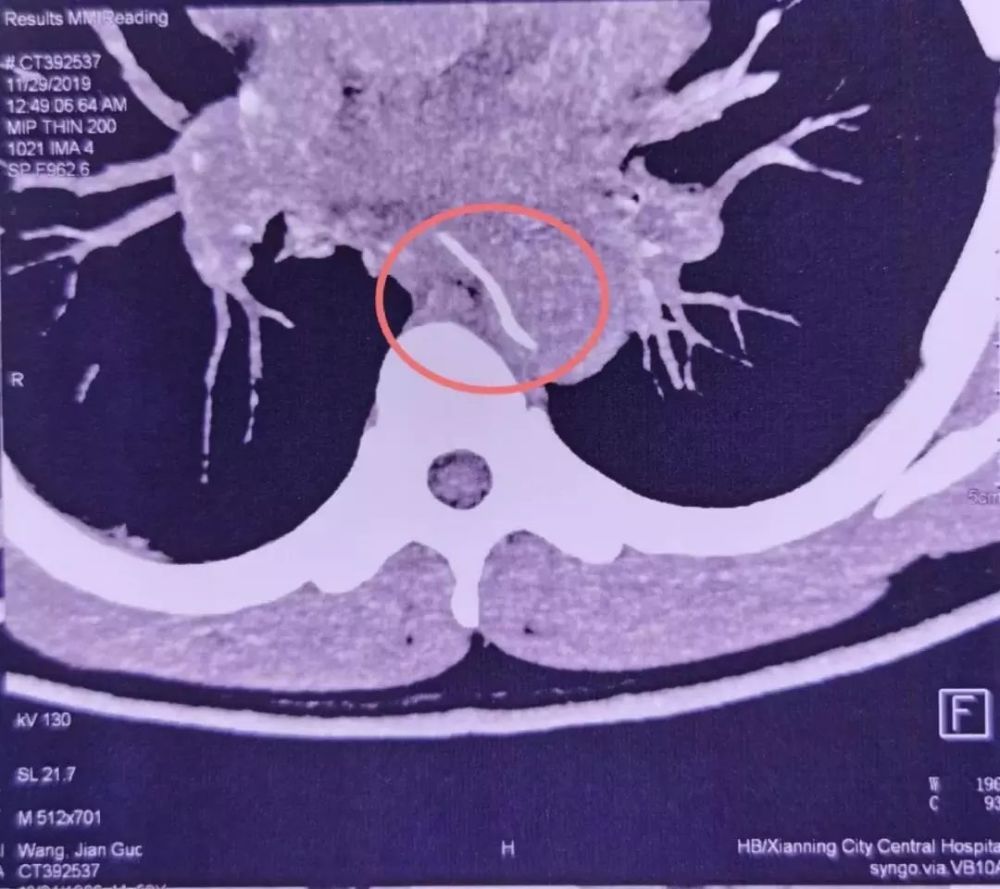

28 号这天,他忽然感觉到剧烈胸痛,所以赶忙到咸宁当地的医院查看。医师很快组织了 CTA(CT 血管造影)。成果发现,一根鱼刺样的异物卡在了老林的食道内,而且现已刺穿了食道壁,扎进了胸主动脉。

图片来自:武汉大学人民医院

第二天一大早,重症医学科的魏捷听值勤医师报告了这个病例。她看到查看成果后,发现鱼刺像一把「弯刀」架在食道和主动脉之间,就像主动脉上突兀地长出了一根刺。